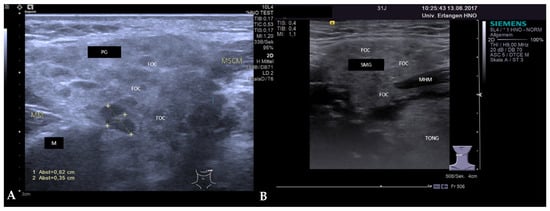

3.2. Findings in Normal Anatomy in Major Salivary Glands